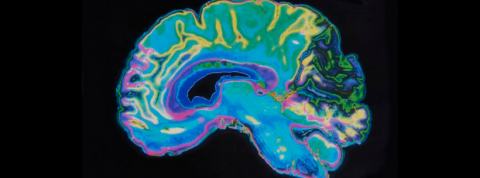

Mémoire éternelle, cerveaux connectés à Internet, intelligence augmentée : le cerveau humain est au centre de toutes les attentions. Scientifiques et expert-e-s de tous bords se penchent à son chevet, et entendent booster ses capacités. À rebours des annonces parfois outrancières des techno-gourous, le neuroscientifique Newton Howard travaille avant tout à réparer le cerveau, grâce à une micro puce baptisée Kiwi.

Newton Howard : Kiwi est une puce composée de plusieurs microprocesseurs que l’on installe dans le cerveau pour réparer ses fonctions défaillantes. Cette puce est différente des autres types d’implants parce qu’elle est fabriquée à partir d’un matériau unique : le nanotube de carbone (CNT). Ce matériau se forme dans la nature à de très hautes températures, on le retrouve par exemple sur l’or. Il possède des propriétés particulières : c’est un excellent conducteur (il est plus conducteur que le cuivre) et est très solide (il est plus rigide que le plastique). Ces deux propriétés font que notre puce Kiwi est à la fois très sensible et très solide : on peut la placer dans des environnements instables ou compliqués, elle donnera d’excellents résultats. Kiwi fonctionne donc très bien avec les neurones du cerveau : elle capte les signaux électriques pour réparer les neurotransmetteurs.